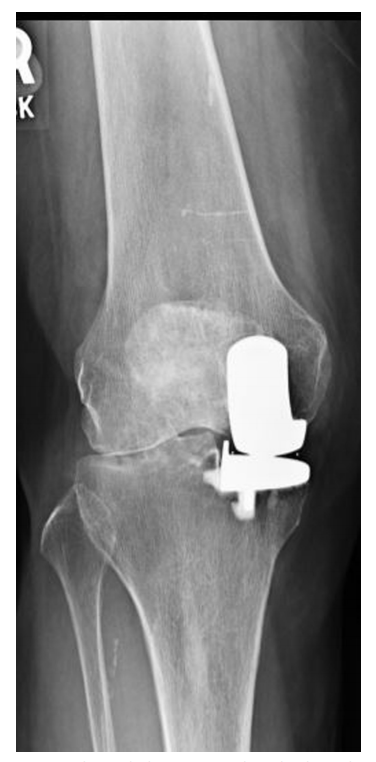

Kozinn和Soctt的经典限制性纳入标准在现代研究中得到了极大的扩展,这些研究表明UKA在年轻患者、肥胖患者、髌股疾病患者以及那些非常活跃的患者中取得了成功。无论如何,正确的患者选择对于确保UKA的成功结果仍然至关重要。对于所有前内侧OA(图1)、畸形可纠正(图2)、膝关节韧带完好、膝关节活动范围保留、屈曲挛缩小的患者,都可以考虑内侧UKA。

图1:计算机断层扫描显示前内侧骨关节炎。

图2:(A)站立正位X线片显示内侧关节间隙丢失。(B)外翻应力X线片显示可矫正的对齐和对侧关节空间的保存。